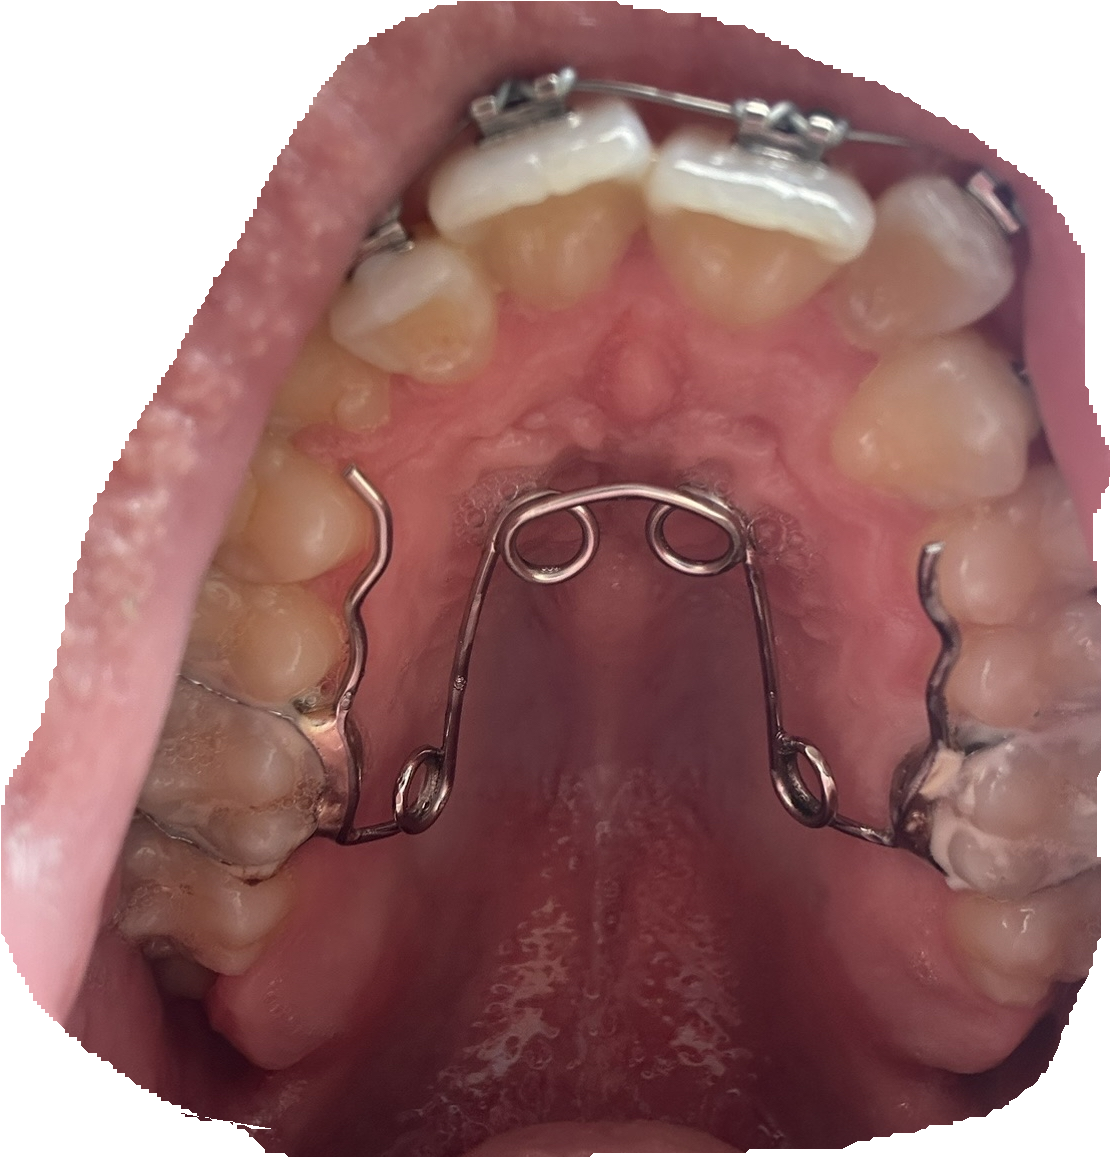

Hi I’m 17.5 years old and wanted to ask the community for a way to convince my orthodontist to give me a palate expansion as I’m chopped and I want to save my bloodline and one way to ascend is a palate expander as I’m on braces rn because I have a right tilt in my smile now I told my orthodontist that I want a palate expander he told me that It will cause an imbalance now for me I have been breathing through my nose my whole life and I can breath through my nose while playing soccer and basketball for a good amount of time then I need short breaths from my mouth now my question stands how do I convince my orthodontist I really really want to have a beautiful child with a beautiful wife so whatever can help hell if I’m too old then I’m fucked for life please be truely honest with me friend I need to know